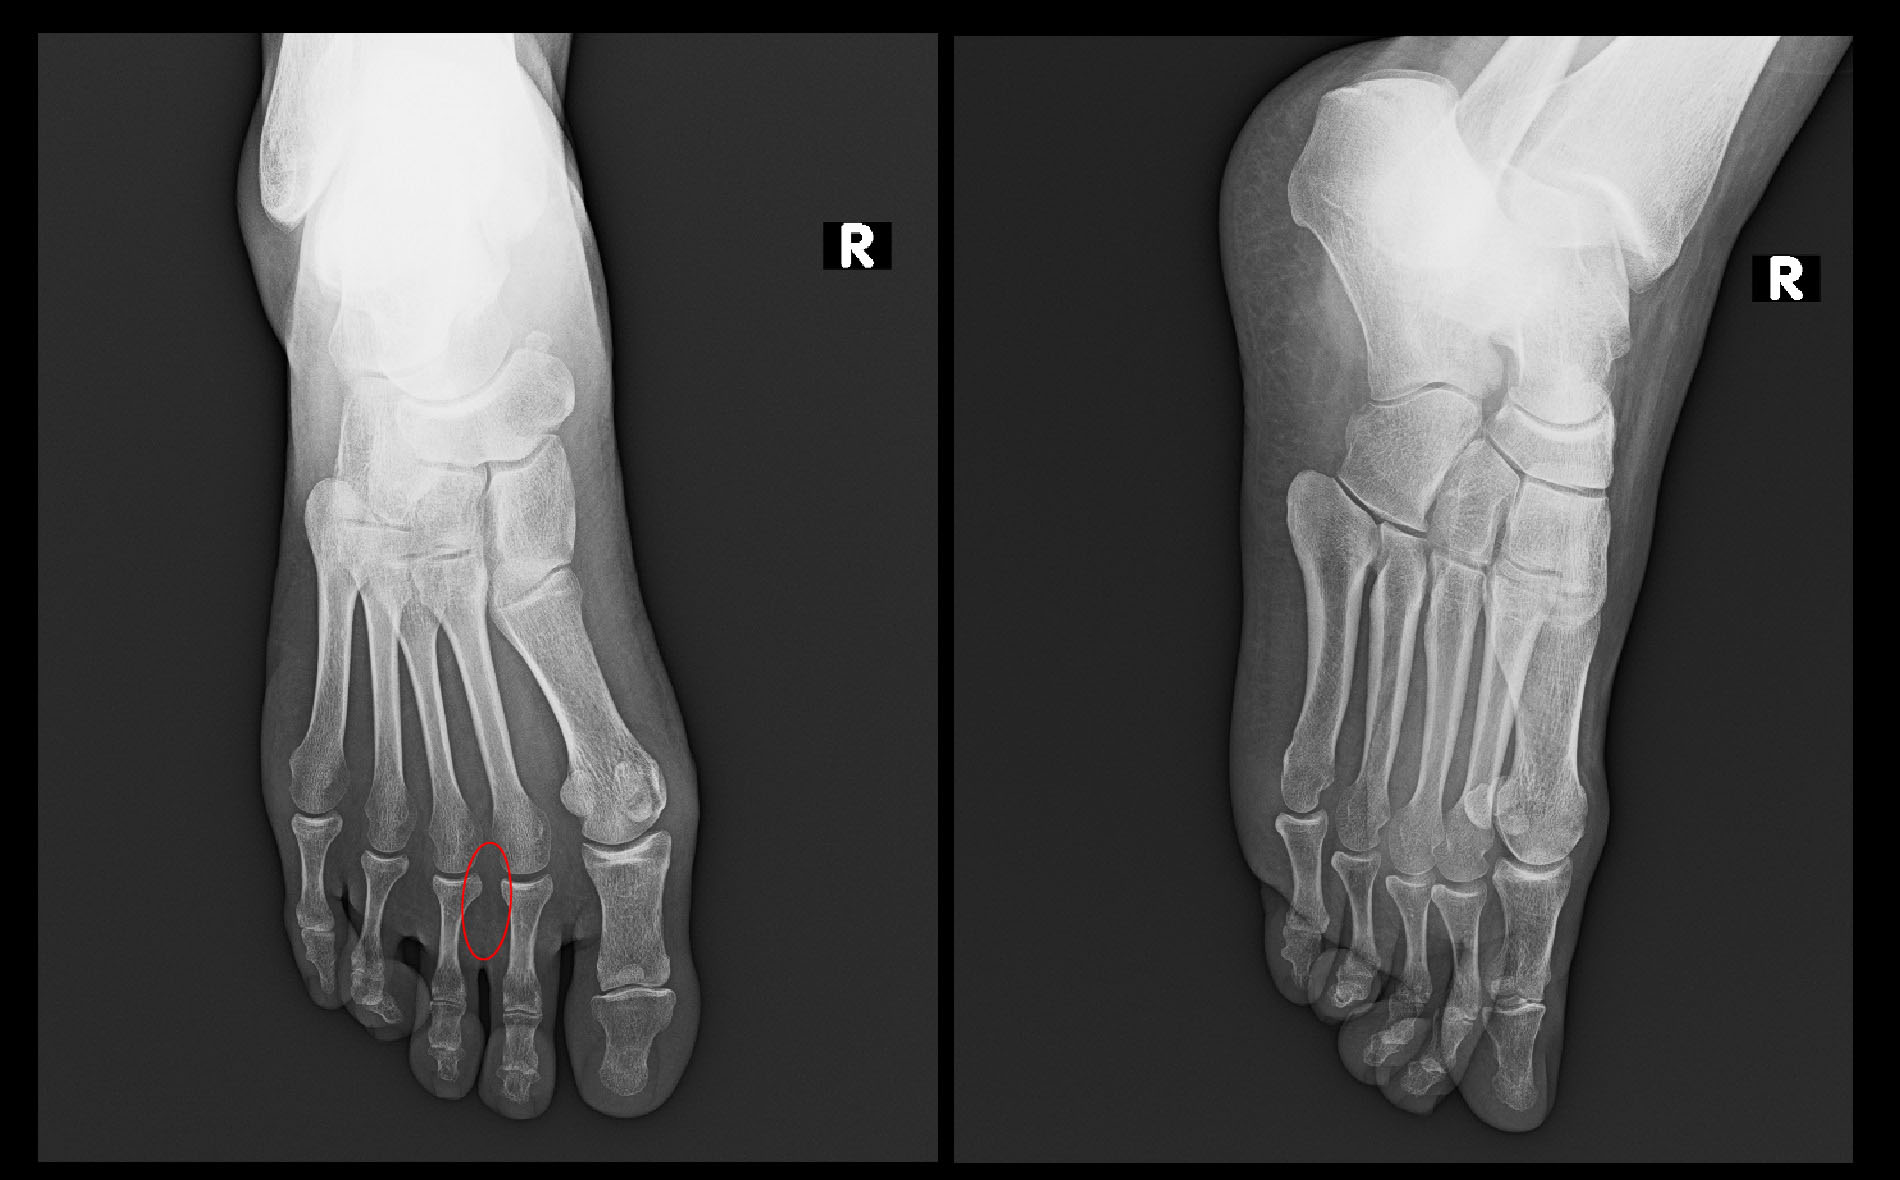

まずは、患者さんが右足痛はモートン病だと思うと言って受診された55才の女性の症例です。

患者さんは令和4年9月27日レントゲン像の赤丸部分の足底領域の痛みで受診されました。8月下旬に発症し、立ち上がり時の歩行開始時の痛みはVAS8(とても痛い)でした。手で右足の前方部を握るようにすると痛みが出るということでした。赤丸部に圧痛は認められませんでした。

55才女Xp1.jpg

私はモートン病と診断した症例はなく、経験的には足部のMP関節炎の症例が多いと説明しましたが、同関節炎の場合、同関節を足背部から圧痛をチェックすると圧痛+となりますが、この患者さんでは同関節部の圧痛は確認されませんでした。